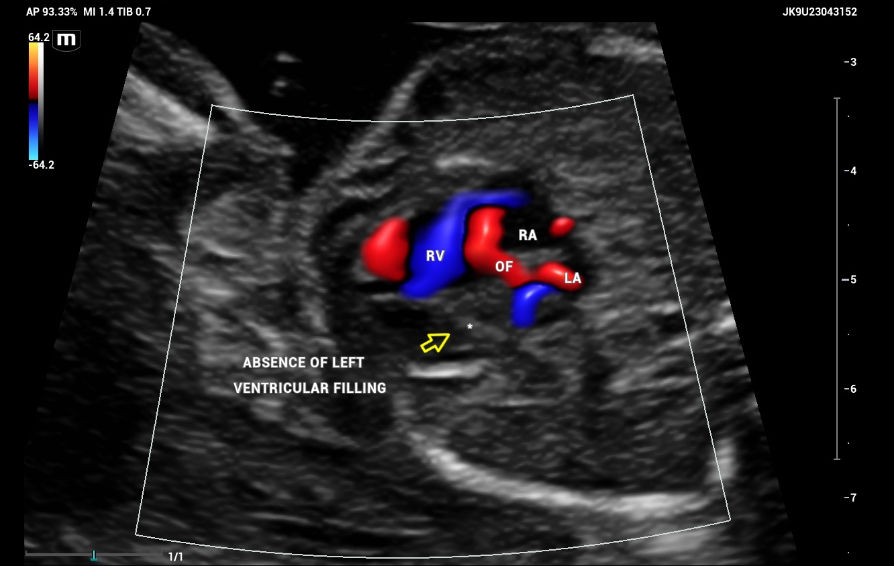

The emergence of the aorta was difficult to visualize, and hypoplasia or aortic atresia was suspected during the exam. Color and power Doppler were used to visualize systolic and diastolic flow to obtain ventricular filling images. Absent color Doppler could be visualized by entering the LV through the mitral valve(Figure 9), in contrast to a normal echocardiography showing normal filling and size of symmetric ventricles.

CASE Fetal echocardiography. Absent color Doppler could be visualized by entering the left ventricle (arrow) through the mitral valve. Right ventricle (RV) with normal filling. Oval foramen with left-right shunt. Ultrasound compatible findings with Hypoplastic left heart syndrome (HLHS)

Figure 9. CASE Fetal echocardiography. Absent color Doppler could be visualized by entering the left ventricle (arrow) through the mitral valve. Right ventricle (RV) with normal filling. Oval foramen with left-right shunt. Ultrasound compatible findings with Hypoplastic left heart syndrome (HLHS).